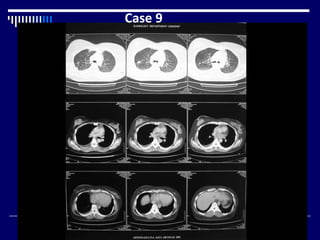

Case 9

• CT chest with contrast ( lung + mediastinal window) (1)

• Large, heterogeneous mass right breast (1)

• Skin thickening + nipple retraction (1)

• Nodules right upper lobe (1)

• Reticulations right upper lobe (1)

• Bilateral pleural effusions (1)

• Hypodense area in liver (1)

• Dx = CA breast with lymphangitis carcinomatosa and

liver metastasis (2)

What Next = FNAC breast (1)